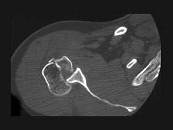

问题 男,28岁,摔伤后肩部疼痛,活动受限,结合影像学表现,最可能的诊断是?(?)

选项 A.柯莱斯骨折 B.肱骨头骨折 C.肱骨外科颈骨折 D.加莱阿齐骨折 E.蒙泰贾骨折

答案 B